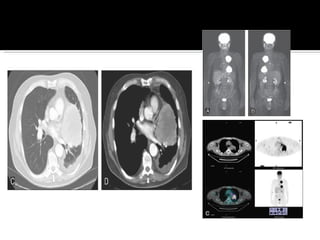

Historia clínica Examen físico Lab  BH,QC Citología seriada esputo. Broncoscopia [biopsia] Medistianoscopia [afección ganglios] Rx AP y lateral. TAC   pulmones, mediastino, hígado, suprarrenales. PET   metástasis. No detecta <15mm.  RM cerebro si hay metástasis. Gammagrama óseo.

Evaluación ganglios mediastinales: Estadio (I,II) PET (-): cirugía. PET (+): biopsia. Mediastinoscopia cervical Mediastinostomia Ultrasonido endoscopico transesofagico Broncoscopia  Enfermedad avanzada, usar método  menos invasivo, en cirugía muestra de todos ganglios.

Historia clínica Examenfísico Lab  BH,QC Citología seriada esputo. Broncoscopia [biopsia] Medistianoscopia [afección ganglios] Rx AP y lateral. TAC  pulmones, mediastino, hígado, suprarrenales. PET  metástasis. No detecta <15mm. RM cerebro si hay metástasis. Gammagrama óseo.

Evaluación ganglios mediastinales:Estadio (I,II) PET (-): cirugía. PET (+): biopsia. Mediastinoscopia cervical Mediastinostomia Ultrasonido endoscopico transesofagico Broncoscopia Enfermedad avanzada, usar método menos invasivo, en cirugía muestra de todos ganglios.